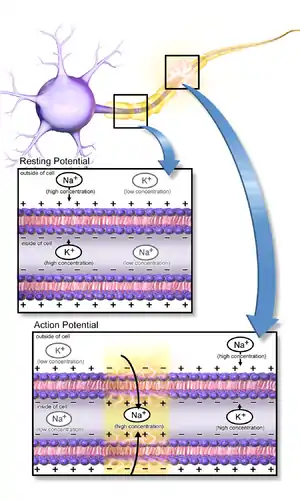

Neurons function in the central nervous system by generating signals from synapses, and this only works in the proper chemical environment.[4] An electrical signal is mediated by the sodium channels and leaky potassium channels in which intracellular K+ ion concentration is higher than its corresponding extracellular concentration, whereas extracellular concentrations of Na+, Ca2+, and Cl− ions are higher than the corresponding intracellular concentrations. This uneven distribution of ions is maintained by the Na+/K+ ATPase pump which actively pumps Na+ out and K+ into the cell in a ratio of 3:2 per ATP used. A neuron has a resting membrane potential of -70mV due to the leaky potassium channels.[5] As a neuron depolarizes due to Na+ ion influx through the sodium channels, the membrane reaches a threshold potential and then fires an all or none action potential, which either propagates down the axon or passes on to the other neurons via several gap junctions that link them.[4]

A chemical signal (synaptic transmission) begins with the action potential that propagates down the axon of so-called presynaptic terminal to trigger Ca2+ influx, which causes the synaptic vesicles to fuse and release neurotransmitters, via exocytosis, to the synaptic cleft.[5][6] Released neurotransmitters then bind their specific neuroreceptors at the postsynaptic membrane, or activate their specific ligand-gated ion channels, to fire an action potential that can be either excitatory or inhibitory, depending on the nature of the ligand-gated ion channel. Neurotransmitters are removed from the synaptic cleft by either enzymatic degradation or re-uptake by the same presynaptic neuron, via endocytosis or specific neurotransmitter transporters.[4]

The suppression of synaptic transmission occurs because the presynaptic impulse temporarily fails to trigger the release of neurotransmitters, which, coupled with the altered ion conductance and a change in postsynaptic neuroreceptors, makes synapses unresponsive to neurotransmitter binding, thereby inhibiting postsynaptic excitation.[5]

Hyperpolarization, on the other hand, is employed to reduce neuronal activity by establishing a high threshold potential for firing across an action potential. This energy-conserving response is due to the continuous inward current of K+ ions, which help maintain the membrane ion gradient until the resistance is broken and anoxic depolarization begins.[5]